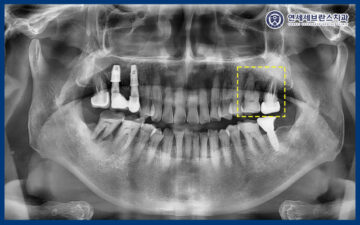

자세히 확인하기 위해

파노라마 촬영을 해보니,

왼쪽 두 치아 뿌리 끝으로

염증이 생겨있었습니다.

현재 다른 임플란트들은

전부 전신질환이 없었을 때

심었던 것들이라 하셨고,

고혈압, 고지혈증, 당뇨에 디스크까지 있어